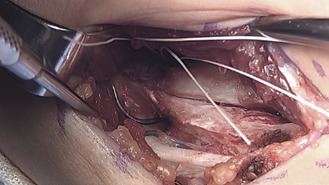

Beginning distally at the sublime tubercle, the ligament is split longitudinally proximally to the ligament footprint origin at the base of the medial epicondyle. The ligament is explored for any acute injury pattern. Additional suturing may be employed for distinct proximal and distal tears.

On either side of the concavity of the sublime tubercle, 2 converging 3.5 mm drill holes are made. These tunnels are transitioned with a curved curette and a doubled vicryl suture is passed with a curved needle.

A 2.7 mm drill hole is made at the apex of the sublime tubercle 4 to 5 mm distal to the joint line but proximal to the ulnar tunnels. A 3.5 mm swivel lock anchor loaded with collagen coated fiber tape is placed in the tapped drill hole.

Graft Passage

With the arm held in full supination and 30° of flexion primary repair of the distal footprint tear, if present, is performed.

One arm of the tendon graft is docked, with a #2 ortho cord suture with a baseball stitch with one arm of the internal brace. The second arm of the tendon graft is cut to an appropriate length, and the second #2 Ortho cord suture is placed. The second arm of the tendon graft is then docked proximally, followed by the second arm of the internal brace.

The internal brace suture arms are first tensioned and tied using a knot tier. Five throws are placed in the suture arms. The tendon graft sutures are then tensioned and tied as well. *Note that the internal brace is tensioned and tied first to preset the tension on the joint. (Figure 17)